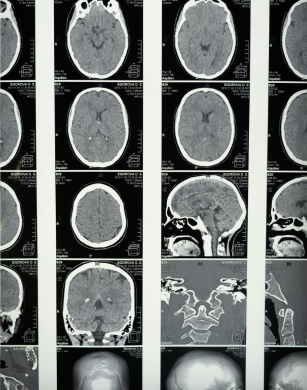

El estudio tuvo como objetivo explorar los mecanismos cognitivos del cerebro con TAS utilizando técnicas de neuroimagen. En concreto, se empleó resonancia magnética funcional (Functional Magnetic Resonance Imaging, fMRI, en inglés) para cumplir con el propósito. Para ello, se realizó un metaanálisis que incluyó 37 estudios previos, comparando las activaciones cerebrales de personas con TAS y de controles sin TAS. Estas tareas incluían la presentación de rostros emocionales, situaciones sociales específicas y otras tareas que provocan respuestas emocionales.